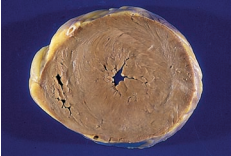

A 62-year-old man is brought to the emergency room in a

disoriented state. Physical examination reveals jaundice,

splenomegaly, and ascites. Serum levels of ALT, AST, alkaline

phosphatase, and bilirubin are all elevated. A liver biopsy

demonstrates alcoholic hepatitis with Mallory bodies. These

cytoplasmic structures are composed of interwoven bundles

of which of the following proteins?